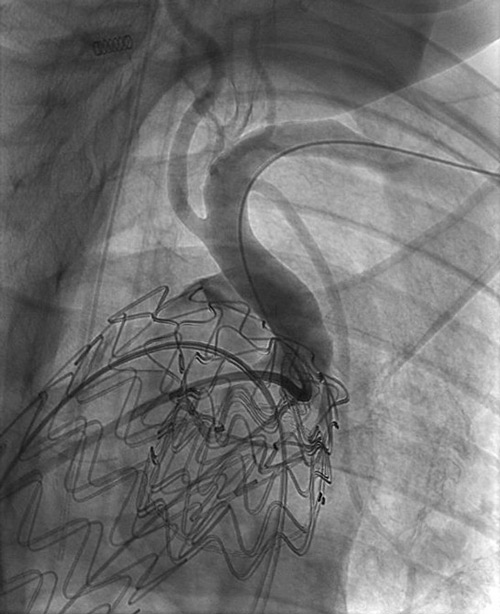

Step 2 (after 8 weeks):

Distal optimisation and future treatment option

- Further extension of the 37 x 200 mm Gore® TAG® Conformable with a large diameter tapered 37/31 x 150 mm TAG® Conformable

- At the same time, preparation for a potential later extension into the abdominal aorta, should the disease progress and become treatment-indicated in this segment.

- Reduction of the risk of a distal stent graft–induced new entry (dSINE) and improved adaptation to the patient’s anatomy.

37 TAG® Conformable in 37 TBE -> Long overlap!